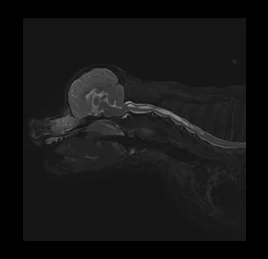

• 허혈성 척수병증

• 척수공동증